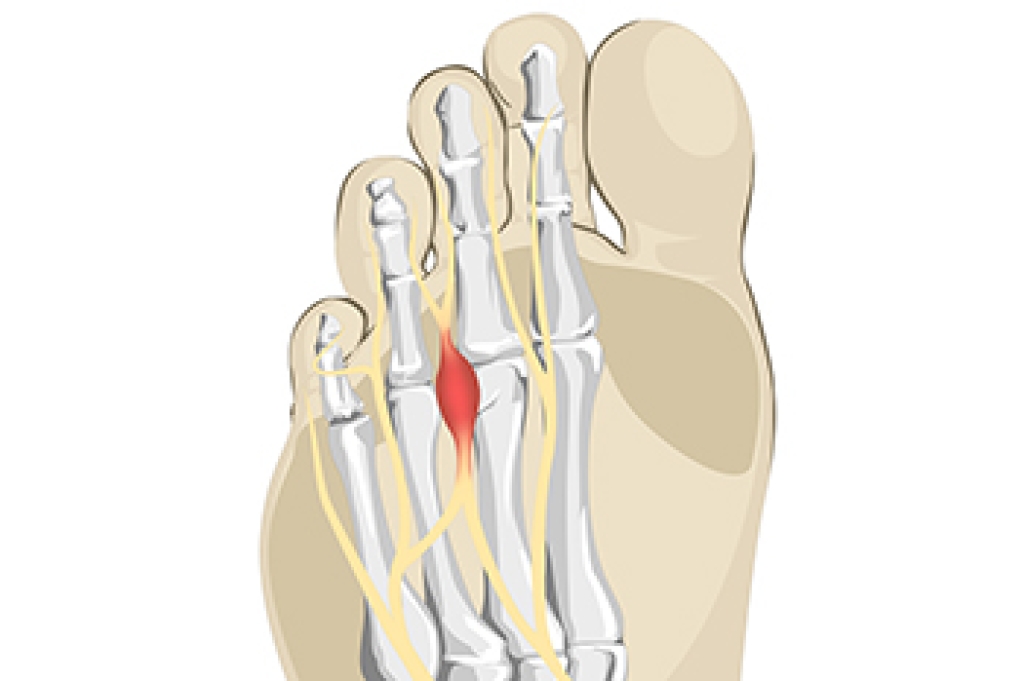

- Clubfoot, where tendons are shortened, bones are shaped differently, and the Achilles tendon is tight, causing the foot to point in and down. It is also possible for the soles of the feet to face each other.

- Polydactyly, which usually consists of a nubbin or small lump of tissue without a bone, a toe that is partially formed but has no joints, or an extra toe.

- Vertical talus, where the talus bone forms in the wrong position causing other bones in the foot to line up improperly, the front of the foot to point up, and the bottom of the foot to stiffen, with no arch, and to curve out.

- Tarsal coalition, when there is an abnormal connection of two or more bones in the foot leading to severe, rigid flatfoot.

- Cleft foot, where there are missing toes, a V-shaped cleft, and other anatomical differences.

- Macrodactyly, when the toes are abnormally large due to overgrowth of the underlying bone or soft tissue.